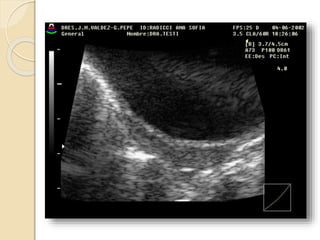

Poliquistosis Ovárica:

Se describe este síndrome como cambios

escleroquísticos en el ovario, mas

amenorrea, infertilidad e hirsutismo.

Ecográficamente vamos a ver

agrandamiento de ambos ovarios con

quistes subcorticales de menos de 1cm.,

mas incremento de las dimensiones del

estroma y fibrosis subcapsular.